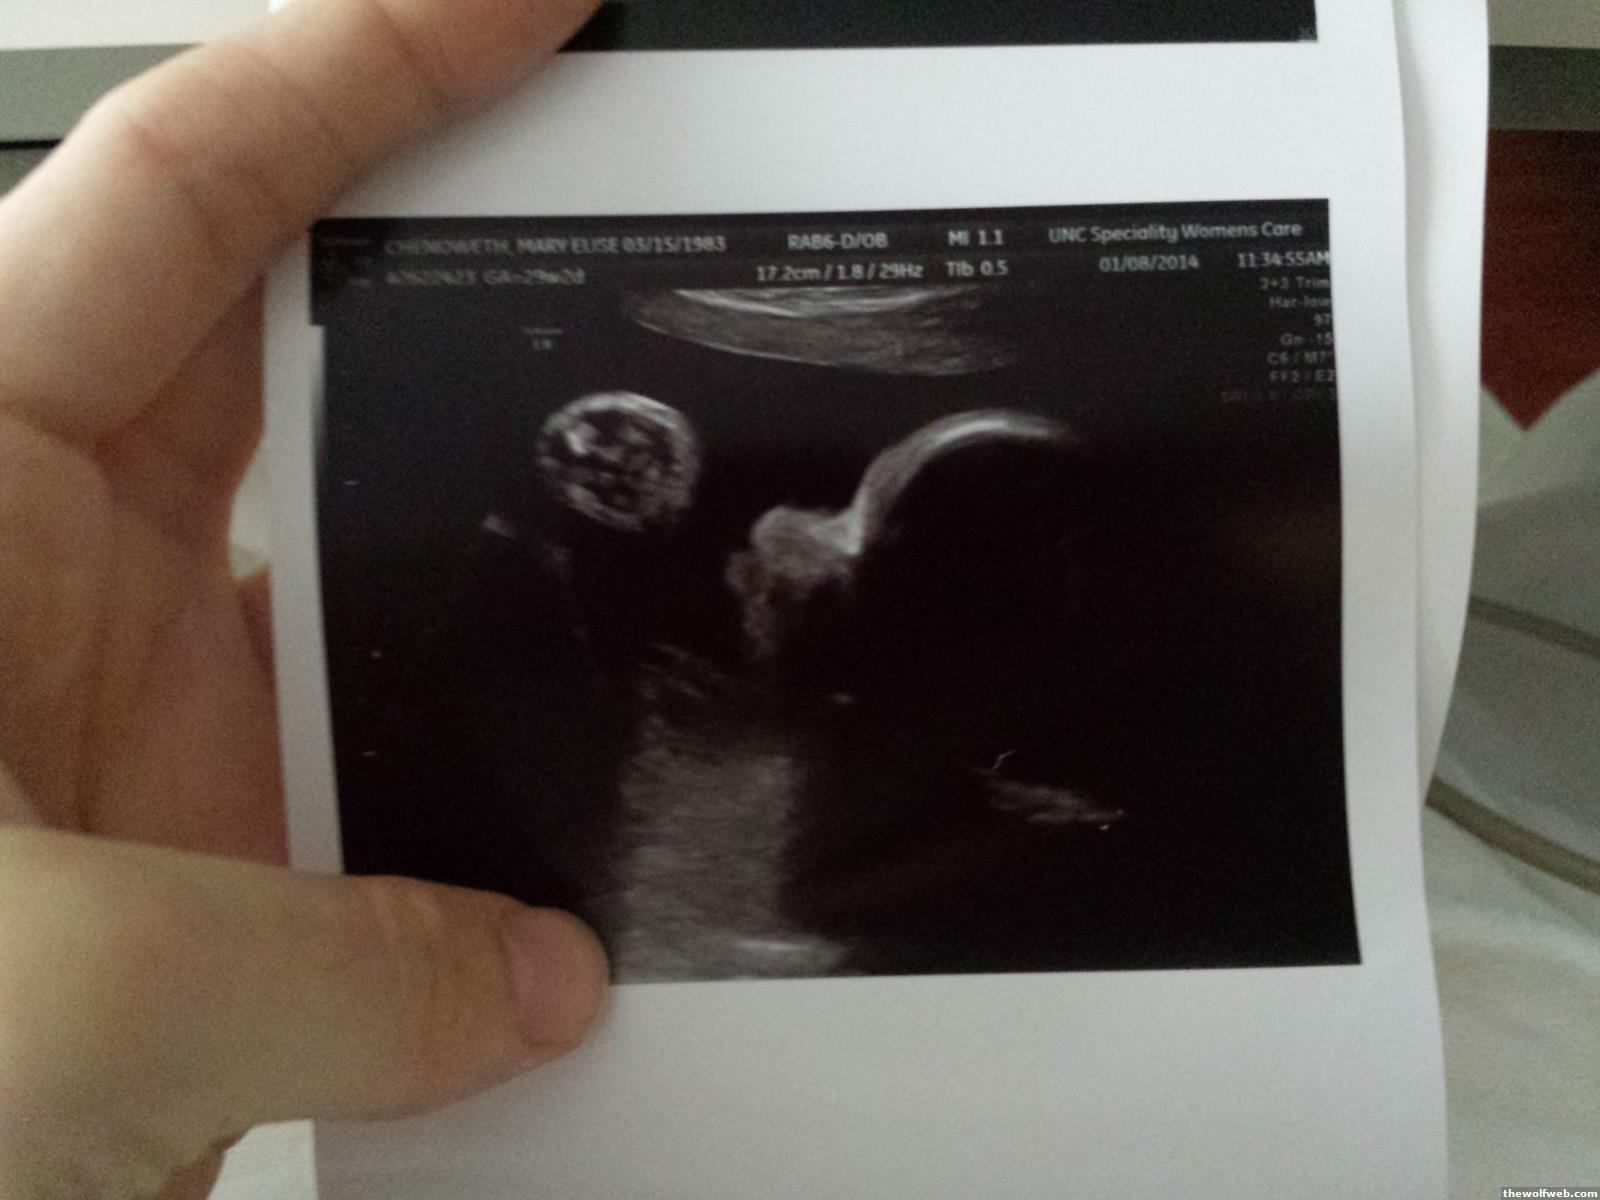

Saw the high risk specialist. Got a 4D photo of my squishy faced baby. He is fine. Very healthy. About 4 pounds. I have to stay at least one more night and then they will decide what to do if the bleeding doesnt start again and the contractions are manageable. If I bleed heavily again I will be admitted until the baby is born. Due date is March 24.

Check out my wolf!

is that a metroid on the left?

is that Ridley on the right??

Technically it is his fist on the left.

An odd profile angle on the right.

success fetus?